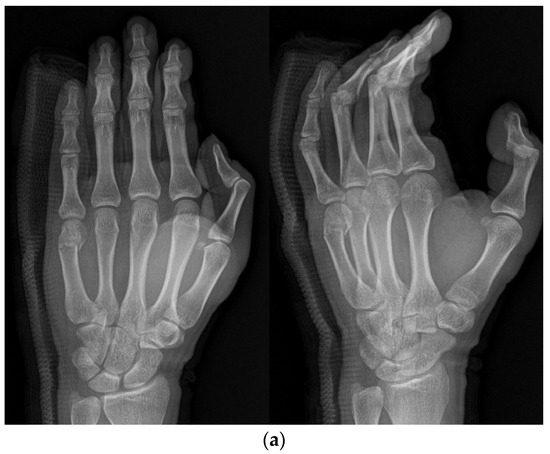

The combined method involved the placement of an intramedullary pin followed by parallel K-wire fixation. Initially, an intramedullary nail was inserted into the metacarpal bone to stabilize the fracture, typically through the base. Following intramedullary pinning, K-wires were placed across the distal part of the intramedullary nail, and the pin was inserted halfway through the dorsal aspect of the nail, touching the nail and making an additional accurate reduction possible. Another pin was inserted on the volar aspect of the nail (Figure 3a,b).

(a) Radiograph of an 18-year-old male patient with displaced little-finger metacarpal neck fracture. (b) Radiograph of a 16-year-old male patient who underwent the IPKP method using one intramedullary nail and two additional K-wires.